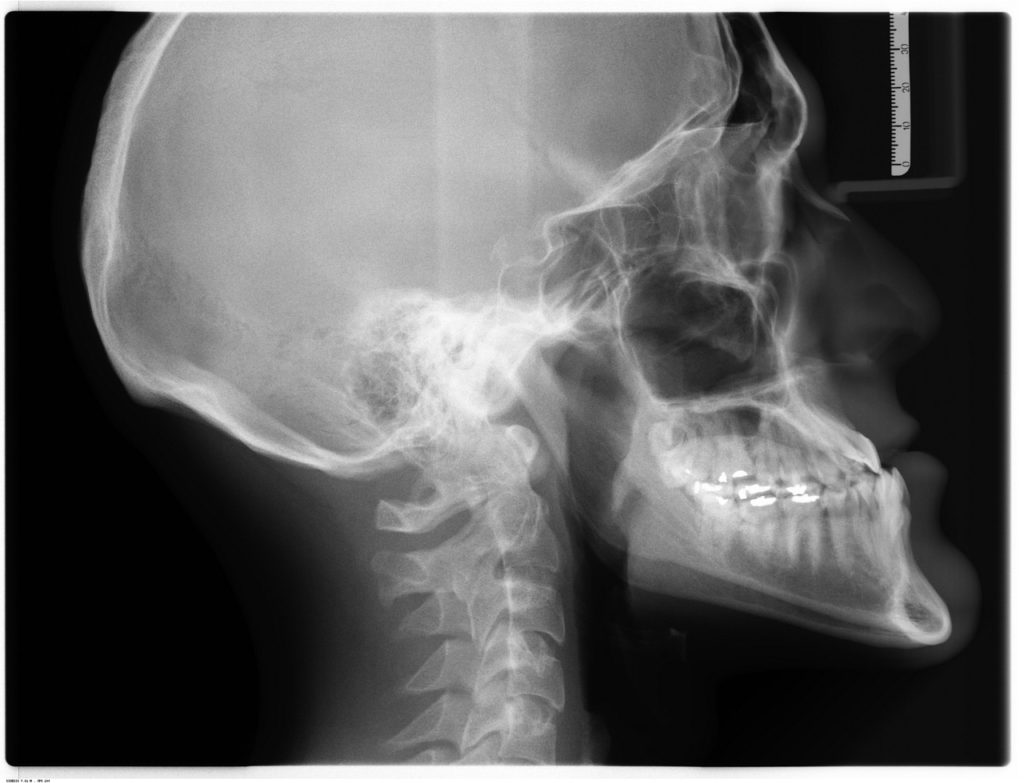

- Correction des classe II squelettiques par système de wilson modifié

- Disjonction maxillaire d’expansion transversale sur implants type MSE

- Les mini-implants en orthopédie dento-faciale :

- Protocole de Pose De Mini-vis sur Differents sites.